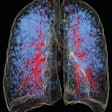

Thoracic Imaging: Page 37

Optellum unveils lung cancer analysis software

Lung-RADS category 4X helps diagnose lung cancer

Ultralow-dose CT works for emphysema quantification

IR with CAD permits ultralow lung CT dose

Chest CT with iterative recon achieves x-ray doses